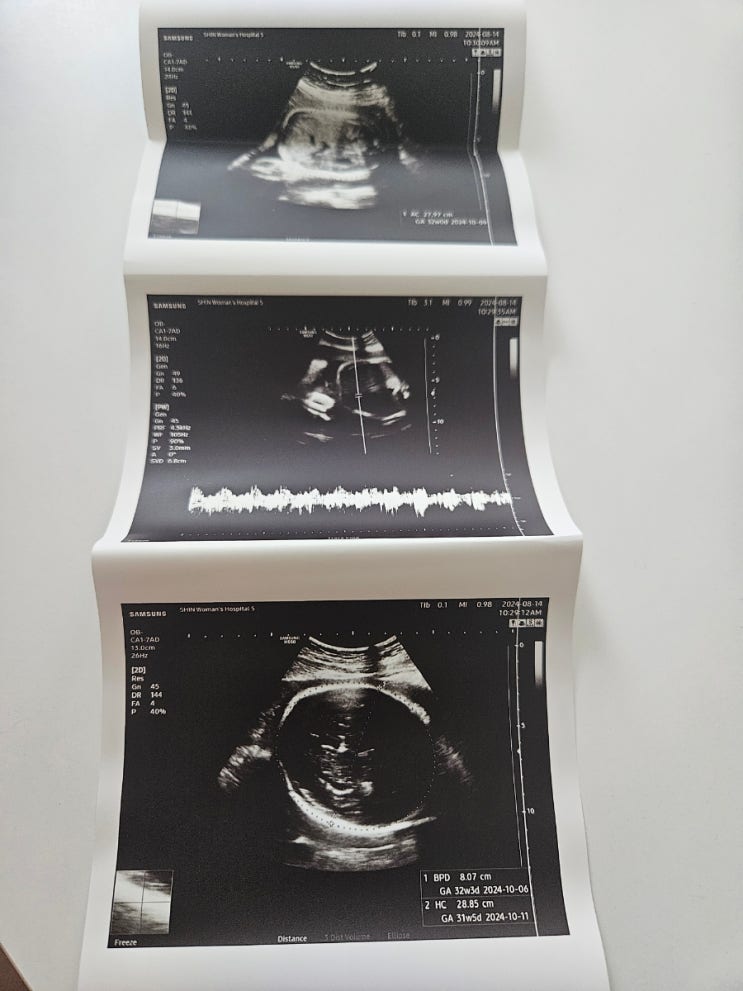

31주차 초음파검사 태아 몸무게 증상 후기

안녕하세요. 뚜맘뚜맘입니다! 오늘은 31주차 저번주에 다녀온 초음파검사 태아 몸무게와 증상에 대해서 글...